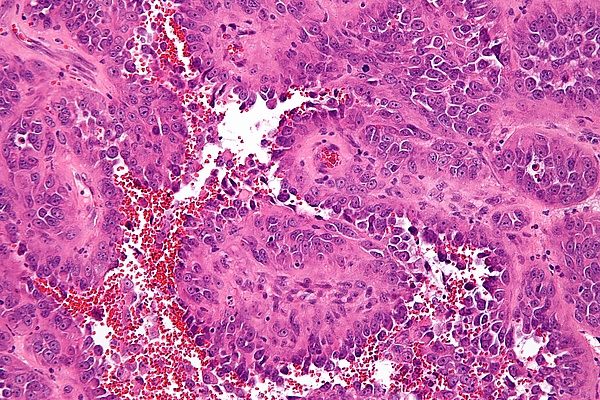

| Микрофотография ангиосаркомы. Окрашено гематоксилином и эозином. | |

Ангиосаркома представляет собой бугристую эластической консистенции опухоль, располагающуюся в глубине мягких тканей и инфильтрующую их. На разрезе состоит из полостей, заполненных кровянистым содержимым. Микроскопически опухоль состоит из большого числа тонкостенных кровеносных сосудов и обильного разрастания малодифференцированных полиморфных клеток. В одних случаях преобладают разрастания клеток типа эндотелия (гемангиоэндотелиома), в других — недифференцированные клетки разрастаются вокруг сосудов наподобие муфт (перителиома, перителиальная саркома)[1].